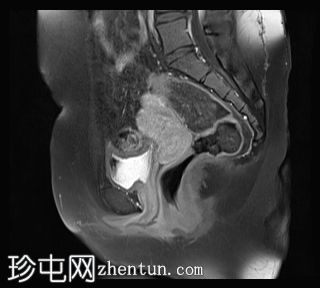

矢状位

T1加权像

C+脂肪抑制像

双侧卵巢位置接近(卵巢相吻),左侧卵巢内可见一边界清晰的囊性病变,大小约3.1 × 2.7 × 2.9 cm,T1加权像呈高信号,T2加权像可见暗点征及内部暗点征。以上MRI特征符合卵巢子宫内膜异位囊肿的诊断。

右侧卵巢可见一囊肿,大小约为 2.8 × 2.0 × 2.2 cm,T1 加权像呈高信号,囊内可见液-液平面,提示囊内含有不同时期的出血性物质。由于对侧卵巢存在典型的子宫内膜异位囊肿,且该囊肿无强化,影像学表现强烈提示为另一子宫内膜异位囊肿。

双侧卵巢囊性病变,MRI 表现符合子宫内膜异位囊肿的特征,左侧较大。未见强化壁结节或实性成分,提示无恶性转化。